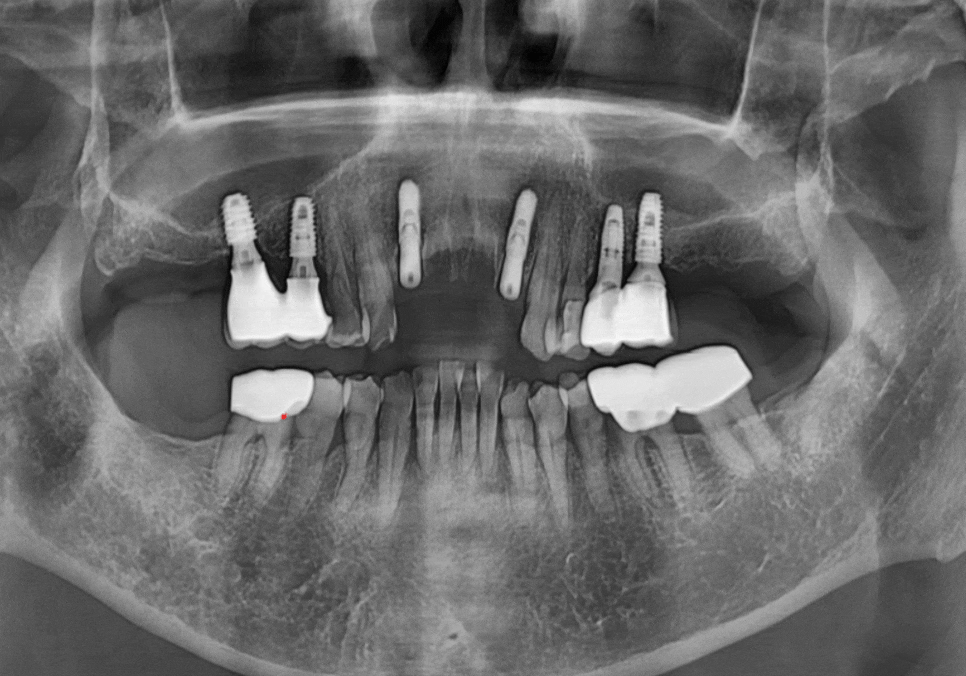

이 기준을 바탕으로

양쪽 끝 위치에만

임플란트를 식립하고

가운데는 보철(브릿지)로 연결하는 방식으로

치료를 진행했습니다.

임플란트 뿌리가 예상했던 위치에

큰 변수 없이 잘 들어간 것을

확인할 수 있었습니다. ^^